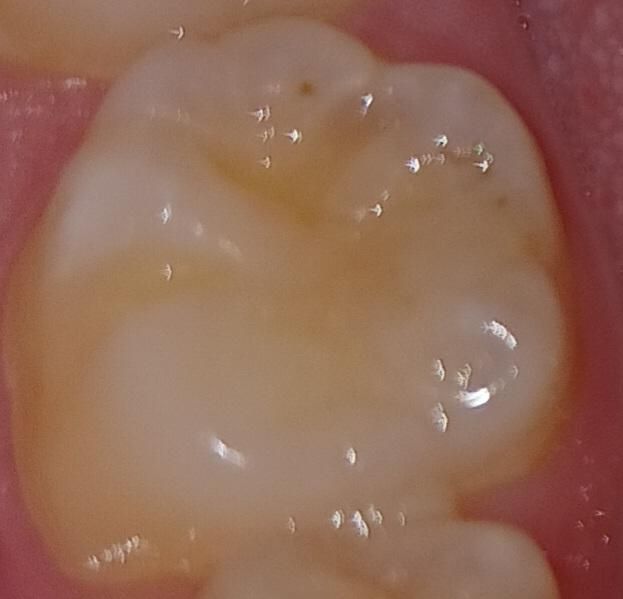

아무 설명없이 이가 갈렸어요 이거 대체 뭘까요

건강검진하러 치과갔는데 엑스레이찍고 좀 보시더니

충치가 있긴한데 초기라 그냥 냅두자고하셨는데

갑자기 아무 설명없이 이를 갈아내서요...

카운터에서 나갈때 뭘 갈았냐고 물어보니

치아요~ 이러길래 말이 안통할것같아서 집에와서 거울보니 치아에 홈이생겼네요;;

이거 뭐 어떻게해야하나요? ㅠㅠ

• 1번 째 사진

치아를 간게 아니라 스켈링을 하고나서 착색제거를 한게 아닐까 생각됩니다. 억지로 치아를 삭제한것처럼 보이진 않습니다.

치아에 착색이 있는 경우에는 표면에 있는 착색 물질을 제거하는 경우가 있습니다. 사진으로 봤을 경우에는 크게 문제가 되지 않을 것으로 생각됩니다. 걱정이 되시거나 해당 부위가 불편하다면 치과에서 진료를 받아보는 것을 권유드립니다.

사진상 이전에 어금니 충치가 있어 떼운 흔적이 있어보이는데 떼운 재료에 대한 교합조정을 한게 아닌가 싶습니다